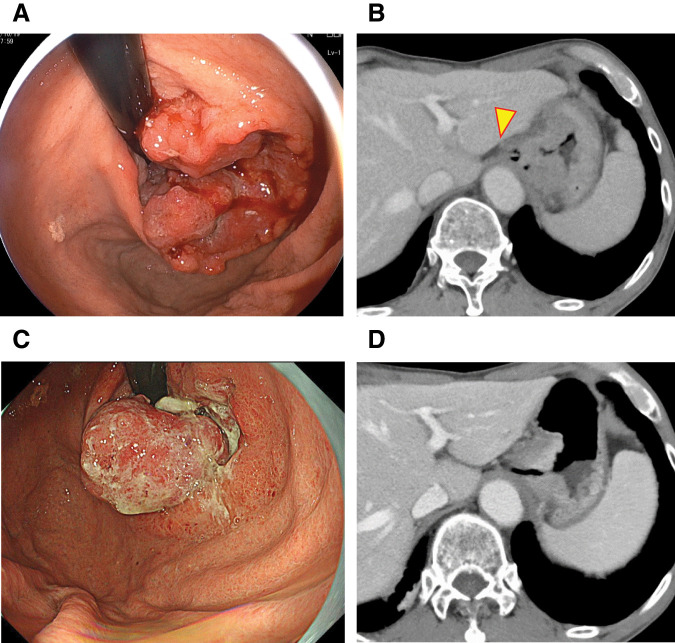

Case presentation: The patient was an 82-year-old man who visited a previous institution for anemia. Upper gastrointestinal endoscopy revealed a type 2 tumor extending from the esophagogastric junction to the upper part of the residual gastric body. Biopsy revealed tubular differentiated adenocarcinoma, and he was referred to our institution. He had a history of distal gastrectomy for a gastric ulcer in his 30s. After contrast-enhanced CT, we diagnosed residual gastric cancer (cT4aN + M0 cStage III). After three courses of preoperative chemotherapy with S-1 plus oxaliplatin, the patient underwent open total resection of the residual stomach, lower esophagectomy, D2 dissection, and Roux-en-Y reconstruction and was discharged without postoperative complications. Six months after surgery, thoracic and abdominal contrast-enhanced CT showed no apparent recurrence. However, 1 month later, he began to experience speech difficulties and mobility issues, and head CT revealed a 3-cm tumor in the left frontal lobe. After whole-body contrast-enhanced CT and PET-CT, the brain tumor was confirmed as a solitary lesion with no metastasis to other organs. The patient underwent open brain tumor resection, and pathology diagnosed brain metastasis from residual gastric cancer. Postoperatively, he underwent radiation therapy (40 Gy in 8 fractions) to the tumor cavity. At the time of writing, 24 months have passed since the gastrectomy and 16 months have passed since the removal of the brain tumor, with no significant neurological damage or other evidence of distant metastasis.